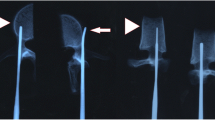

The vertebrae were separated from connective tissue for instrumentation. A small starting hole (approximately 3 mm) in the posterior cortex was created on each side with a rongeur, exposing cancellous bone. A pilot hole was made with a tapered Lenke probe. A titanium 5 × 30-mm (Synthes USS) fixed pedicle screw (Synthes AG, West Chester, PA) was inserted into each pilot hole (Fig. 1) and a 5.5 × 65-mm titanium rod was inserted into each screw head and secured with an endcap and locking nut, tightened to the manufacturer’s recommended torque.

The pedicle morphometry data in our study demonstrate that instrumentation with adult human-sized pedicle screws is possible. Lumbar and thoracic vertebrae had similar pedicle isthmus widths to the human widths measured by Zindrick et al. [27]. Mid to upper thoracic pedicles in our specimens demonstrated a perforated pedicle, in which there was a lateral foramen that bisected the pedicle (Fig. 5). This aspect of the spines may preclude pedicle screw instrumentation of that region. Distance from the posterior to the anterior cortex (AC depth) was considerably shorter than that measured in humans by Zindrick et al. [27]. However, most of the lumbar and lower thoracic vertebrae had AC depths greater than 30 mm, which accepted a 5 × 30-mm screw in this study, without ventral perforation. Mid- to upper thoracic vertebrae had AC depths shorter than 30 mm, making pedicle screw instrumentation less feasible without custom-made short screws.